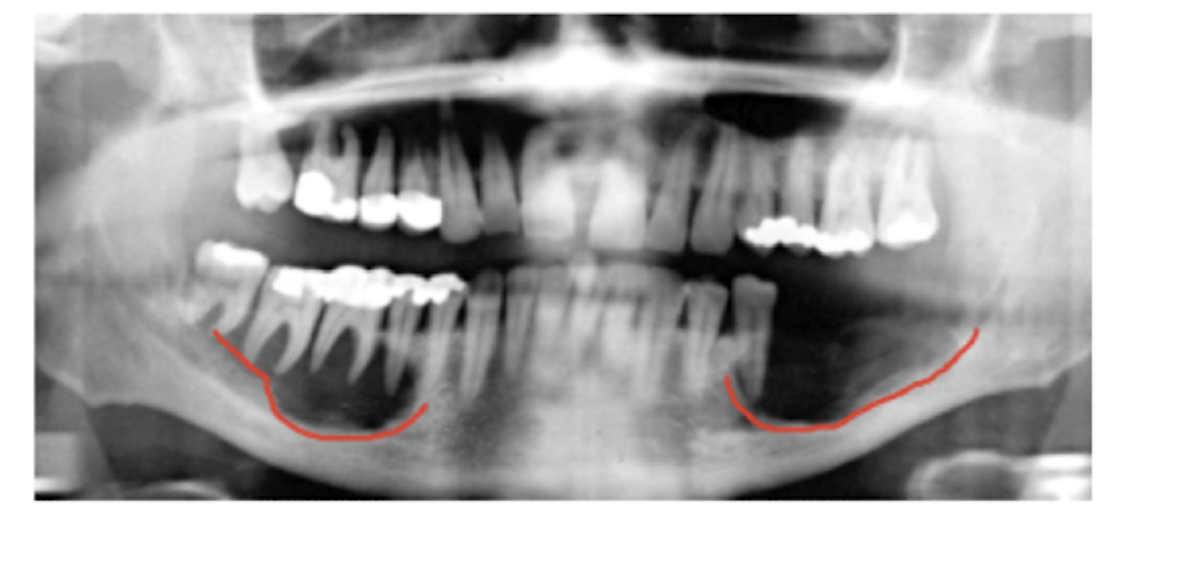

Cherubism

A

Clinical: Symmetrical Bilateral Swelling

Radiographically:

* expansile bilateral multilocular RL

Stops growing after puberty